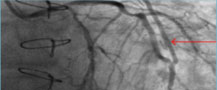

Μετεγχειρητική στεφανιογραφία: Αριστερή Εσω Μαστική αρτηρία (βέλος) έχει συρραφεί στην στεφανιαία αρτηρία (πρόσθιος κατιόντας κλάδος)